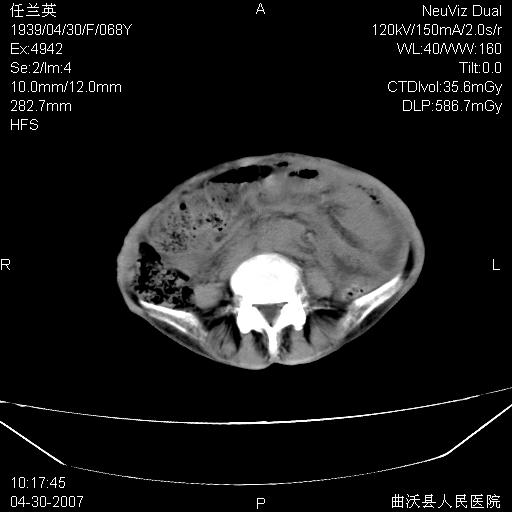

患者,女,68岁,感觉腹部憋涨发硬数天,查b超发现左盆腔有囊性肿物和少量腹水,行ct检查

1.考虑卵巢肿瘤并腹腔广泛性转移可能性大;

2.腹盆腔少量积液。

支持左侧卵巢恶性肿瘤伴网膜、腹膜广泛转移。

支持:左侧卵巢恶性肿瘤伴网膜、腹膜 腹膜后(淋巴结)广泛转移。

网膜、腹膜广泛转移考虑来源于左侧卵巢癌可能性大。不除外来源于消化系的肿瘤。

难的一见 典型 - 网膜饼  冰冻骨盆 可以当教学片了